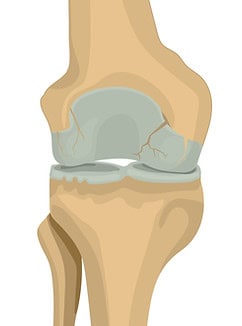

Zweites Stadium

Leichte Arthrose

In diesem Stadium treten erste Anzeichen wie Gelenksteifigkeit, Knieschmerzen und Berührungsempfindlichkeit auf, insbesondere beim Aufstehen nach längerem Sitzen. Die Gelenkflüssigkeit ist noch vorhanden, die Knochen reiben nicht aufeinander und der Gelenkspalt ist nur leicht verengt.

Drittes Stadium

Mäßige Arthrose

Der Knorpelschaden schreitet fort, der Gelenkspalt wird kleiner und die Knorpelschicht wird dünner. Knieschmerzen und Beschwerden können beim Laufen, Gehen, Knien oder Beugen auftreten. Das umliegende Gewebe, insbesondere die innere Gelenkkapsel, entzündet sich und produziert mehr Gelenkflüssigkeit , wodurch das Gelenk anschwillt. Umgangssprachlich spricht man von Wasser im Knie, tatsächlich handelt es sich um eine entzündliche Arthrose.